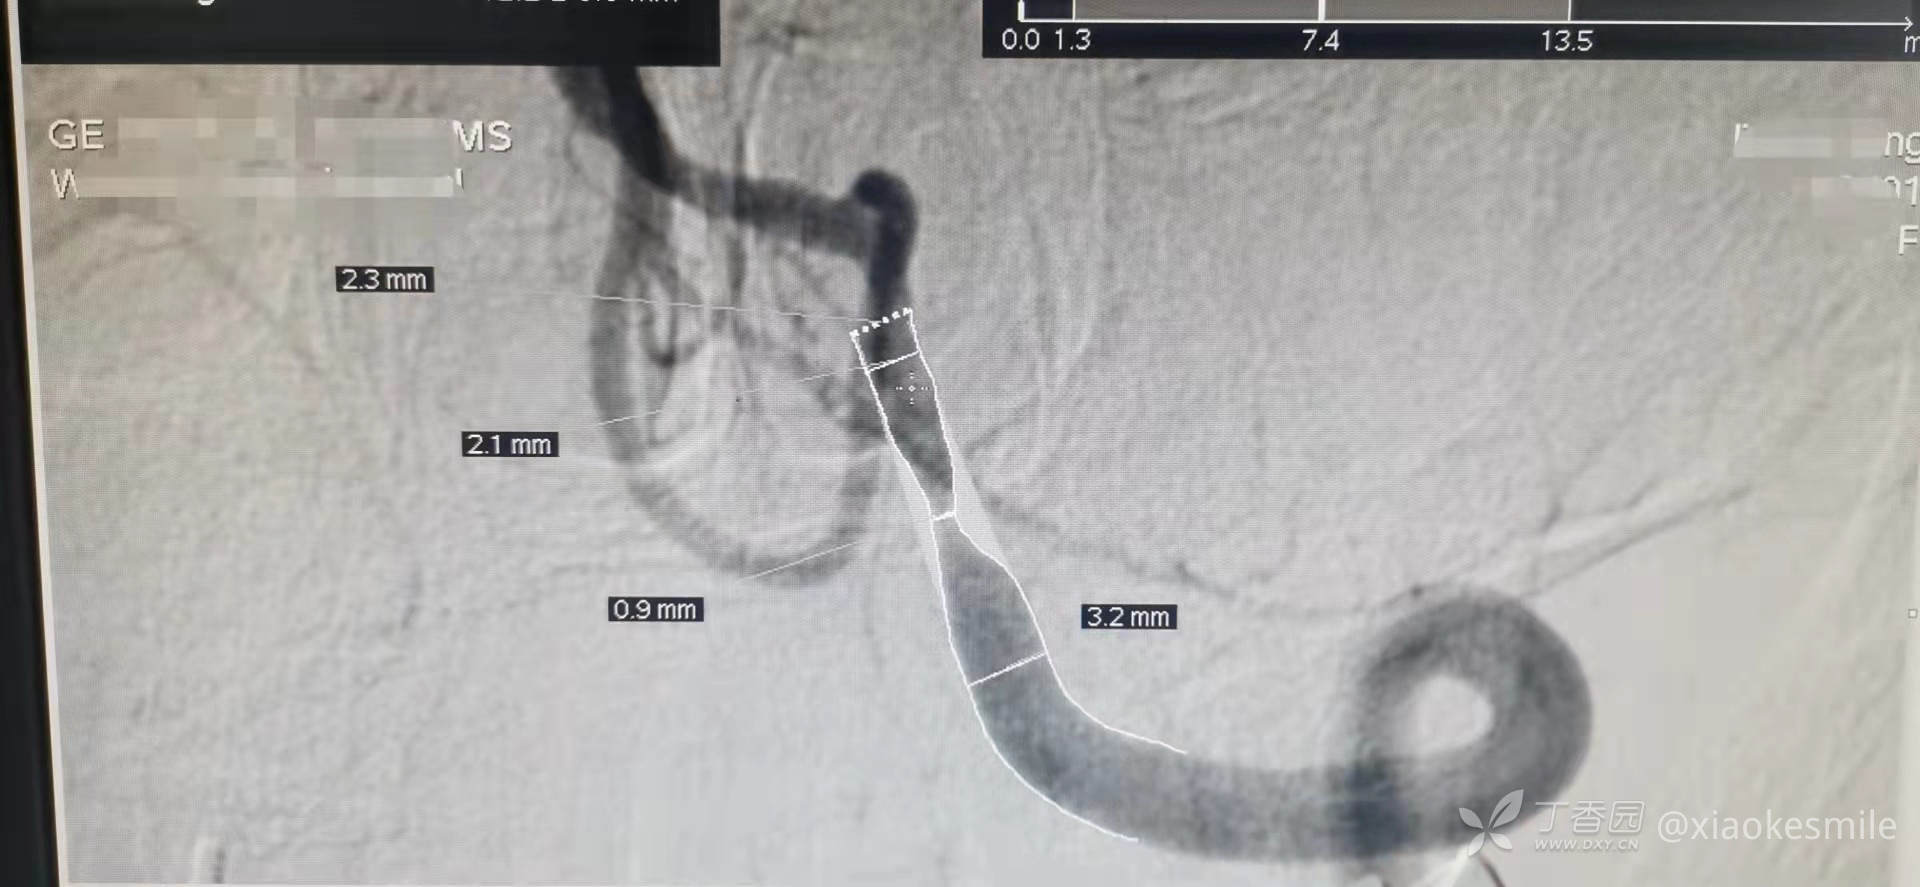

图A-E代表该篇文献提供的5例延髓分水岭梗死患者的影像学特点。右图为椎动脉和小脑后下动脉动脉供应的边界区有类似的逗号状病变。在简化的延髓轴向图中,注意边界区用红色表示。附一例同事提供的病例,也是该种征象,完善DSA检查提示左侧椎动脉重度狭窄(此处提供的为MRA,DSA。看到这可以回忆一下是不是该类患者不少见,只是缺少发现的眼睛)。